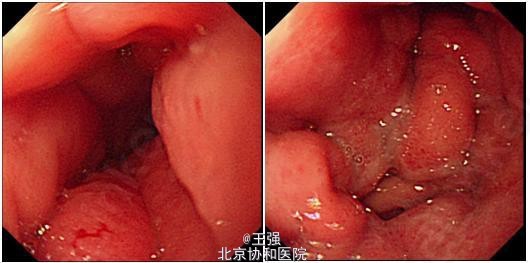

行上消化道造影:胃体大弯侧及胃窦部见巨大充盈缺损,边缘不整,表面凹凸不平,胃壁僵硬,黏膜皱襞中断。胃镜检查:胃底粘膜光滑,蠕动可;胃体皱襞明显增粗、僵硬,无蠕动,粘膜水肿、充血,未见明确溃疡及糜烂,多灶深挖活检8块,质韧;胃体胃腔狭窄,内镜通过有阻力,胃角切迹不能显示,胃窦腔狭小,幽门圆,持续开放。活检病理:(胃体)低分化腺癌。

患者病程短,消耗症状明显,有明确肿瘤家族史,需考虑肿瘤的诊断。但肿瘤指标不高,胃镜及CT表现不典型,胃镜下并没有见到明确的占位或溃疡性病变,只是胃壁的弥漫肿胀,且胃蠕动及排空均较差,以至于误诊为幽门梗阻。这种胃镜表现需要注意深挖活检,必要时可考虑行圈套器粘膜大活检获取更多组织,以明确诊断。 外科评估患者已经存在腹腔转移,患者转肿瘤科化疗。